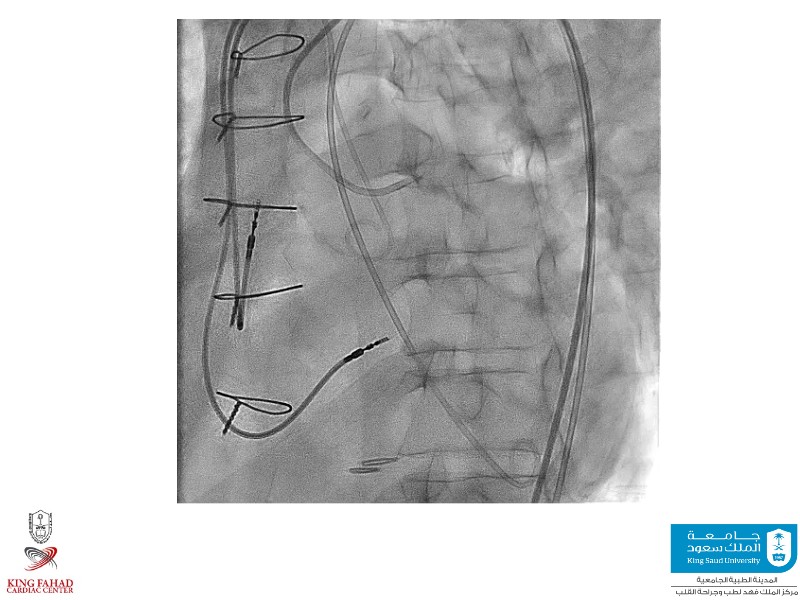

This session helps you anticipate and address complex scenarios such as mitral valve-in-valve, TAV-in-SAV, and valve-in-valve-in-valve procedures. Learn from expert case discussions that explore procedural strategies, technical challenges, and best practices to optimize outcomes in redo structural heart interventions.